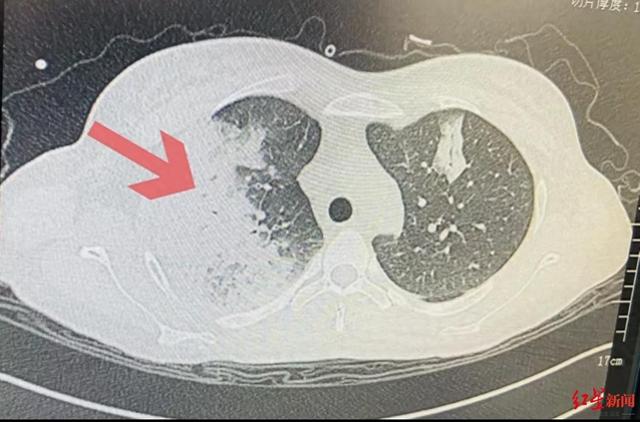

作为一名刚怀孕7周的孕妇,此时小梅已经出现不明原因反复发烧4天了,最高烧到了40℃,还伴有寒战、咳嗽、白痰、眩晕等症状,拍片还发现她的肺部感染严重,已经出现了大面积的“白肺”。

右肺出现大面积“白肺”

红星新闻记者从成都市妇女儿童中心医院获悉,入院后,小梅已出现严重低氧血症,胸部CT显示双肺大面积“白肺”伴胸腔积液,情况已经十分危急了!

眼见着小梅病情越来越严重,剧烈头痛、呕吐、“白肺”面积持续增大、胸腔积液增多,而且已经开始出现肝损伤,离威胁生命的重症只有一步之遥,ICU迅速为她召集了呼吸、药学、放射、重症产科等全院多学科专家会诊。